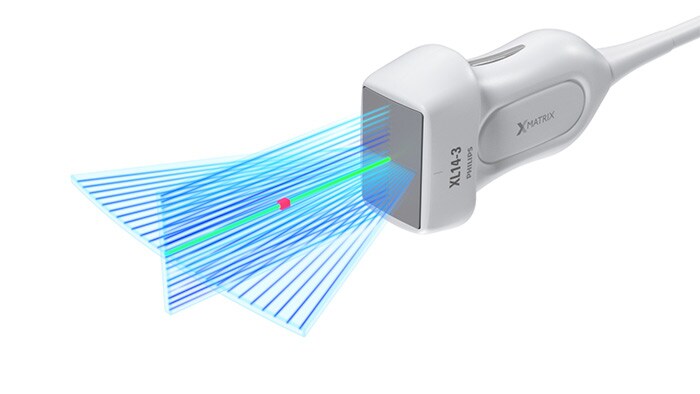

Doppler xPlane

El XL14-3 xMatrix también ofrece funciones de Doppler xPlane. El Doppler pulsado xPlane permite una colocación precisa del volumen de muestra mediante Doppler a través de imágenes de referencia longitudinales y transversales. La principal ventaja: el Doppler xPlane reduce los errores de colocación del volumen de muestra y ofrece una mayor reproducibilidad y coherencia a la hora de tomar muestras de estenosis pronunciadas.